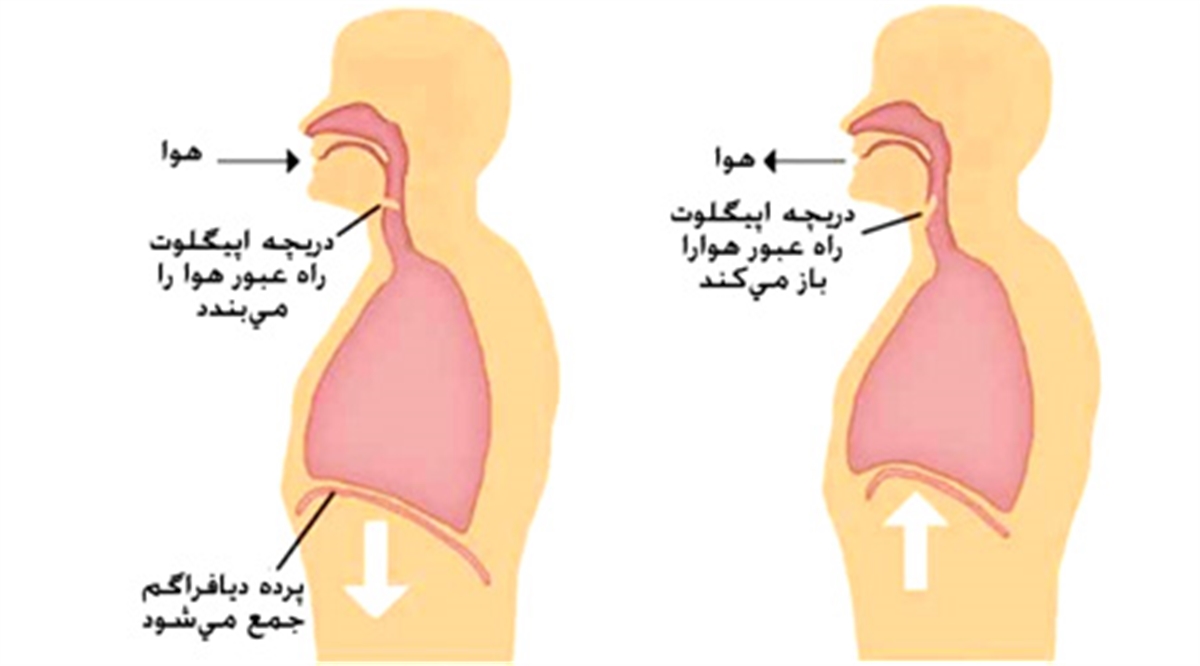

عکس داخل شکم انسان. در این همان طور که مشخص است شکم حالت بیضی شکل پیداکرده و این بیضی که کناره های شکم کشیده شده است. تعداد سلول های بدن انسان حدود ۳۷ ۲ تریلیون تخمین زده شده اند. Abdomen که در زبان عامه به غلط به آن دل نیز می گویند در آناتومی به قسمتی از تنه گفته می شود که مابین دیافراگم از بالا و سطح فوقانی لگن خاصره از پایین قرار دارد. ربات دیدنی ربات انساننمای چینی به صورت یک دختر جوان ساخته شده و جیا جیا نامگذاری شده است این ربات طوری برنامهریزی شده که میتواند صحبت کند و احساسات خود را از طریق تغییرات در چهره حالات.